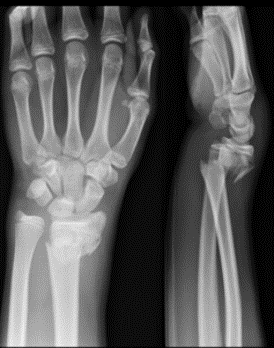

What is the diagnosis?